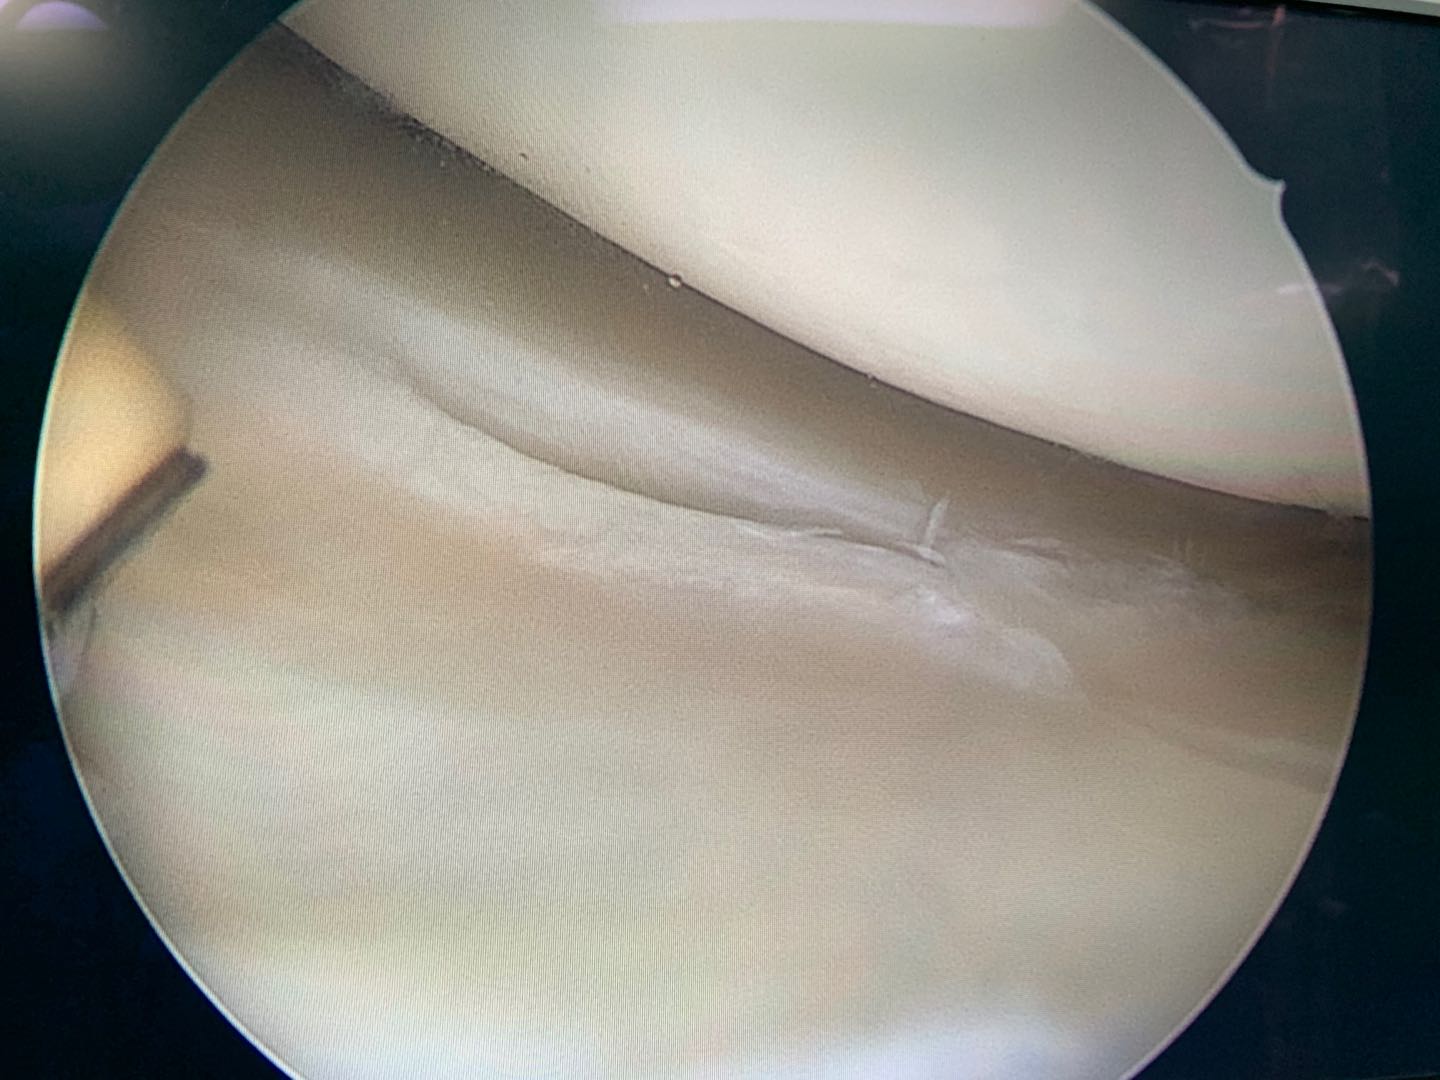

以前手术的病人,典型的半月板撕裂

手术后能恢复吗,需要多久?

能恢复,答案是肯定的,术后经过科学的功能康复断裂,韧带断的话,一般术后9个月-12个月能重返运动,比较剧烈的对抗运动一般最后还是1年后。单纯半月板损伤话,最好是3月-6月后再恢复运动。